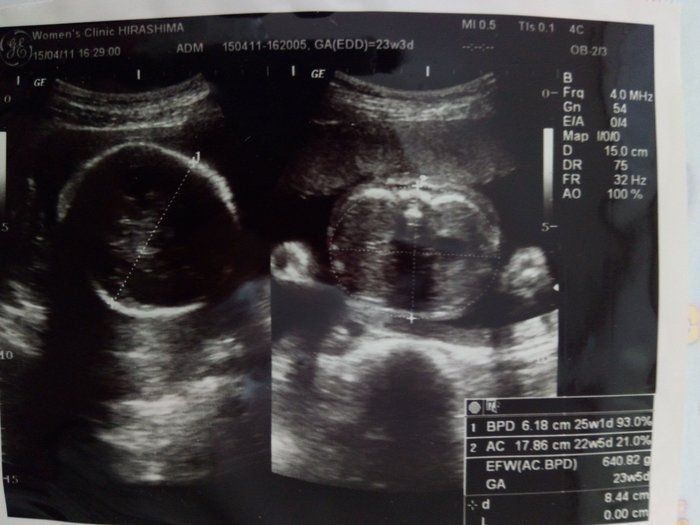

水野谷つむぎさんの妊娠23週目のエコー写真 赤ちゃんの推定体重640g

この日、体重増加の注意が入ってしまいました。(+5kgでした。)けれど、安静指示は解けず、食事量も増えてはおらず、思わず「どうやって体重管理しればいいんですか」と、突っ込んでしまいました。白米を減らすなど、食事の工夫をするようアドバイスされました。